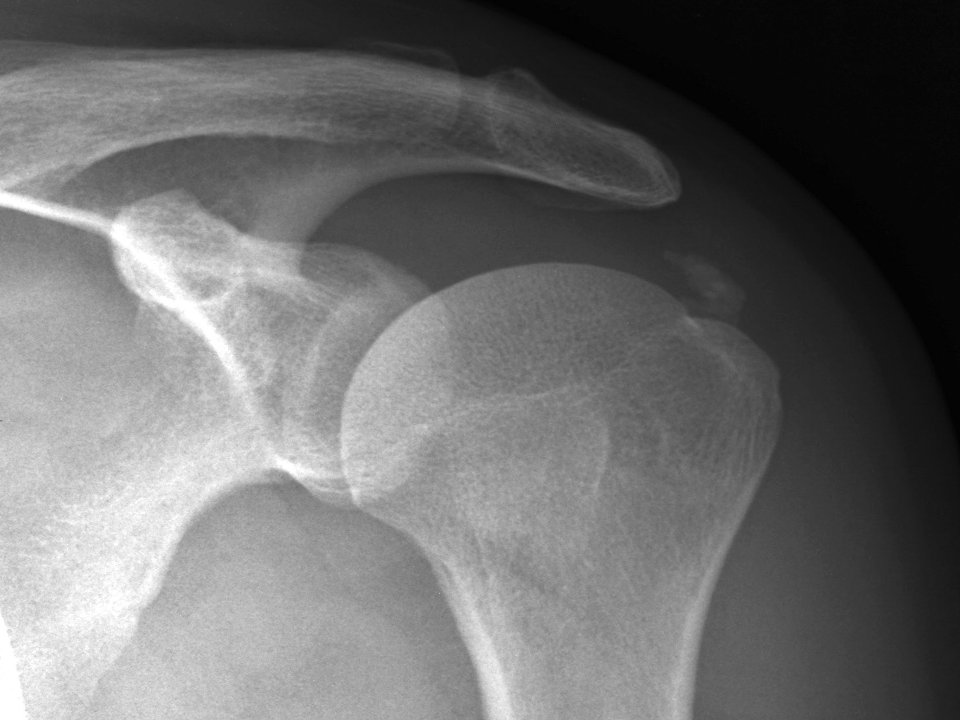

Εξάρθρημα ώμου – αστάθεια

Η άρθρωση του ώμου είναι η πιο ευκίνητη άρθρωση στο ανθρώπινο σώμα. Δυστυχώς όμως η περισσότερη ευκινησία συνεπάγεται και λιγότερη σταθερότητα. Έτσι, διάφορα αθλήματα αλλά και δραστηριότητες της καθημερινής ζωής θέτουν υψηλές απαιτήσεις από την άρθρωση του ώμου εξωθώντας την πολλές φορές πέρα από τα όρια της σταθερότητάς της.